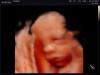

Во сколько недель лучше сделать 4д узи? Планирую идти в 26-28 недель,кто делал покажите фото ,заранее спасибо ☺️

@alexandra_19 клиника современной медицины. Недалеко от Ашана

Врач узи в платной клинике сказала, что лучше делать с 30 до 35 недели)